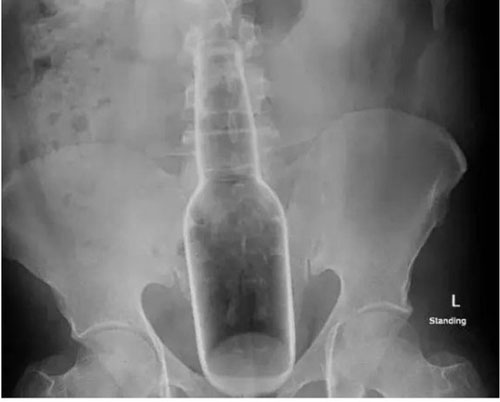

Một bệnh nhân 60 tuổi người Trung Quốc đã phải phẫu thuật trực tràng để lấy ra chai nước mà ông dùng để… gãi hậu môn.